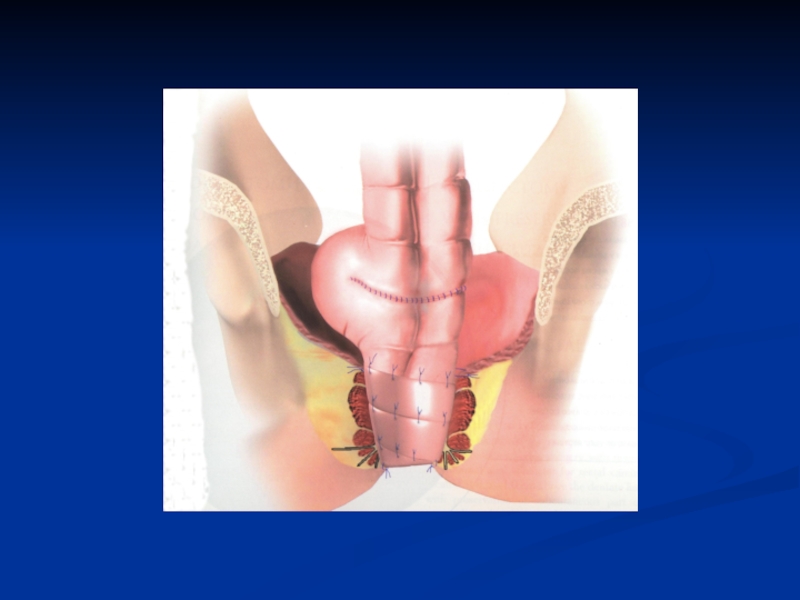

Слайд 70Брюшно-промежностная экстирпация прямой кишки. Мобилизация тазовой брюшины.

Брюшно-промежностная экстирпация  прямой кишки. Мобилизация тазовой брюшины.

Слайд 71Брюшно-промежностная экстирпация прямой кишки. Пересечение сигмовидной кишки.

Брюшно-промежностная экстирпация прямой кишки. Пересечение сигмовидной кишки.

Слайд 72Брюшно-промежностная экстирпация прямой кишки. Отделение кишки от крестца.

Брюшно-промежностная экстирпация прямой кишки. Отделение кишки от крестца.

Слайд 73Брюшно-промежностная экстирпация прямой кишки. Пересечение переднебоковых связок кишки.

Брюшно-промежностная экстирпация прямой кишки. Пересечение переднебоковых связок кишки.

Слайд 74Брюшно-промежностная экстирпация прямой кишки. Мобилизация сигмовидной кишки.

Брюшно-промежностная экстирпация прямой кишки. Мобилизация сигмовидной кишки.

Слайд 75Брюшно-промежностная экстирпация прямой кишки. Основные моменты промежностного этапа операции.

Брюшно-промежностная экстирпация прямой кишки. Основные моменты промежностного этапа операции.